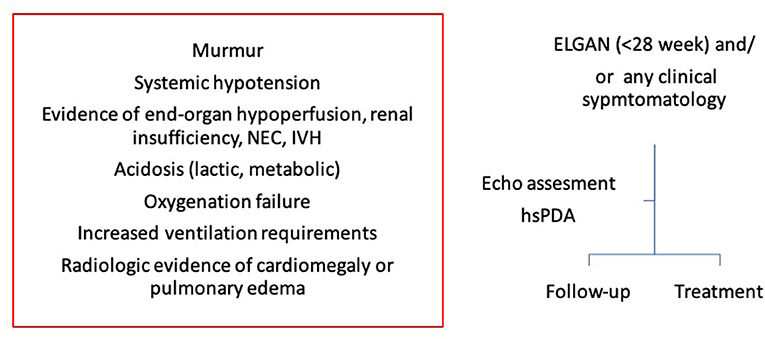

The authors recommend a comprehensive assessment of PDA and its hemodynamic significance before making any clinical decision to treat or not and the clinical decision making should be made in clinical context of the individual infant. A simple algorithm to clinical decision making based upon clinical and echocardiographic assessment, whether to treat or follow up, has been summarized in Figure 11. Moreover, this can be dynamic decision, especially in infants with conservative management and serial assessment on neonatologist performed echocardiography can help in making timely individualized decision making.

Figure 11. A simple algorithm to clinical decision making in extremely low gestational age newborn infants (ELGAN). Clinical decision whether to treat or follow up should be made based upon both clinical and echocardiography assessment. NEC, necrotizing enterocolitis; IVH, intraventricular hemorrhage; ELGAN, extremely low gestational age newborn infants; hsPDA, hemodynamically significant patent ductus arteriosus.